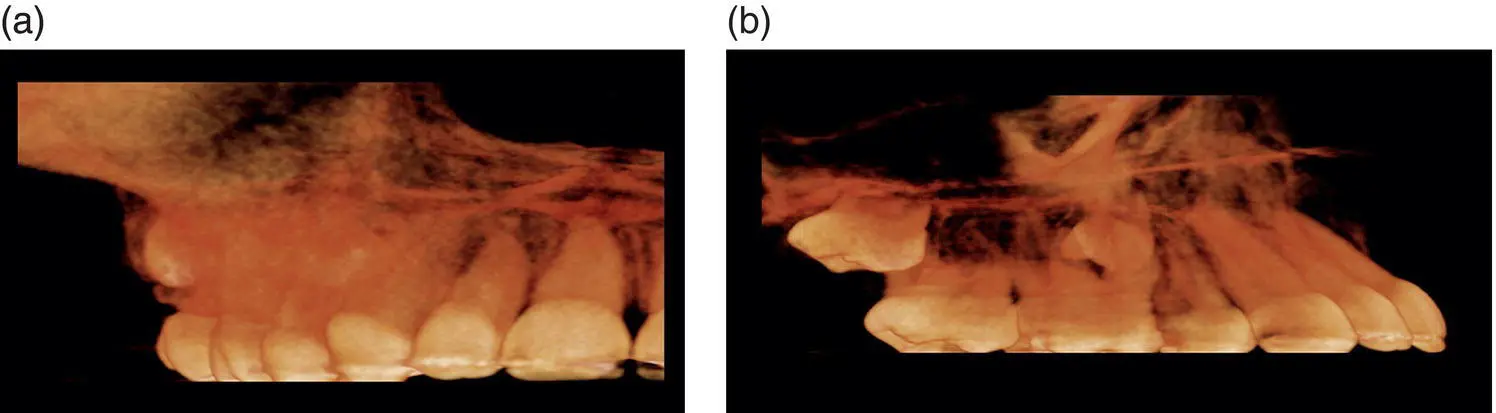

Figure 1.2.Axial (A), coronal (C), sagittal (S), and reconstructed 3D views from a small FOV.